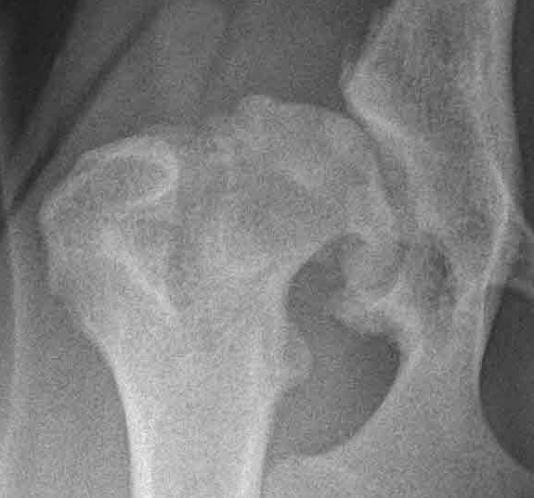

HD E: Røntgenbilde av unormalt hofteledd med sterk grad HD (E) og betydelige artroser.

Diagnosen stilles ved hjelp av klinisk undersøkelse og røntgenbilder som vurderer hofteleddets utforming og eventuell slitasje, med eller uten forkalkninger. Det finnes ulike grader av denne defekten, og røntgenavlesning av hofteleddene graderes i Norge (NKK/FCI) etter følgende skala: Fri (A, B), svak (C), middels (D) eller sterk (E) grad av HD.